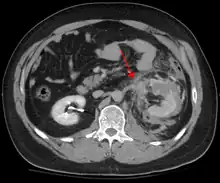

Abdominal CT showing left renal artery injury

Blunt abdominal trauma (BAT) represents 75% of all blunt trauma and is the most common example of this injury.[3] 75% of BAT occurs in motor vehicle crashes,[4] in which rapid deceleration may propel the driver into the steering wheel, dashboard, or seatbelt,[5] causing contusions in less serious cases, or rupture of internal organs from briefly increased intraluminal pressure in the more serious, depending on the force applied. Initially, there may be few indications that serious internal abdominal injury has occurred, making assessment more challenging and requiring a high degree of clinical suspicion.[6]

Deceleration, on the other hand, causes stretching and shearing at the points where mobile contents in the abdomen, like bowel, are anchored. This can cause tearing of the mesentery of the bowel and injury to the blood vessels that travel within the mesentery. Classic examples of these mechanisms are a hepatic tear along the ligamentum teres and injuries to the renal arteries.